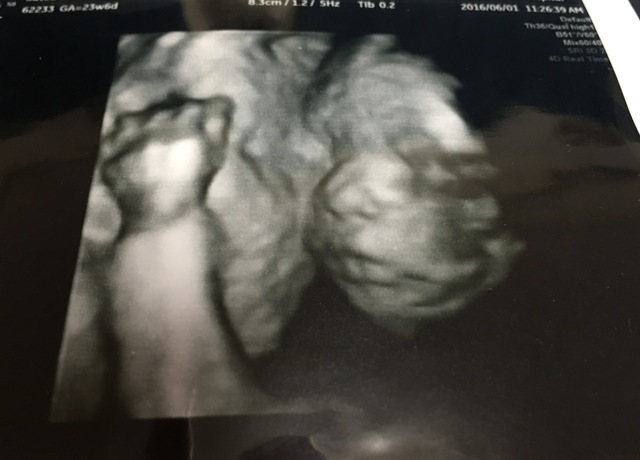

23週6日(23w6d・男の子)|kemi2472 さん(32歳)

エコー写真撮影時のエピソード:

なかなか顔を取らせてくれない子で、これが最初で最後のお顔が見えたエコー写真です。

他のものはへその緒が写ってたり、手で顔を覆ってしまったりで…。もっとたくさんお顔のエコー写真が欲しかったです。